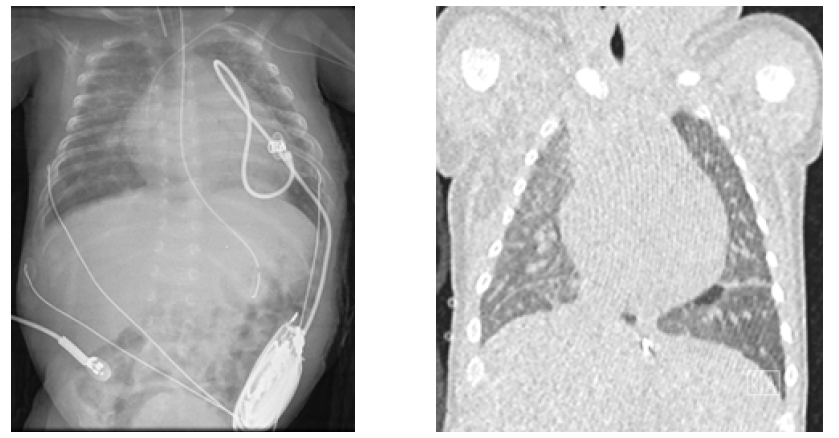

Pulmonary NLE manifestations have rarely been reported in the literature. Most neonates with circulating maternal antibodies have no lung manifestations or only present mild tachypnea or hypoxemia. However, respiratory manifestations may be significant in some cases.32 Pneumonitis, pleural effusion, necrotizing pulmonary capillaritis, and alveolar hemorrhage have been described as clinical manifestations of pulmonary involvement in neonatal lupus (Figure 4).3,34-36 Pereira S. et al. described a clinical case of severe pneumonitis diagnosed on day 17 of life in a neonate with complete heart block and definitive pacemaker.33 The neonate presented with acute severe respiratory failure requiring mechanical ventilation and oxygen therapy, with diffuse infiltrates in chest radiograph and ground glass-like computed tomography (CT), which responded to intravenous methylprednisolone pulses followed by oral prednisolone. Pulmonary hypertension associated with respiratory disease has also been reported as a rare neonatal lupus manifestation. Maltret A. et al. described the clinical presentation, management, and outcome of a series of four neonates who developed reversible pulmonary hypertension associated with autoimmune congenital complete heart block.34 The diagnosis was suspected on transthoracic echocardiography at a median of 42 days of life (range 10-58) and confirmed by right heart catheterization in all neonates. All had some degree of hypoxemia and respiratory distress reversible under oxygen and nitric oxide. Lung CT disclosed ground glass anomalies in all. Management included steroid therapy in three patients, associated with sildenafil in two. Pulmonary hypertension resolved at a median of four weeks after treatment start in the three neonates who received treatment, and after one year in the neonate who did not receive specific treatment.

Figure 4 Pulmonary involvement with multiple focus of neonatal lupus pneumonitis depicted on chest radiography (left) and computed tomography (right)